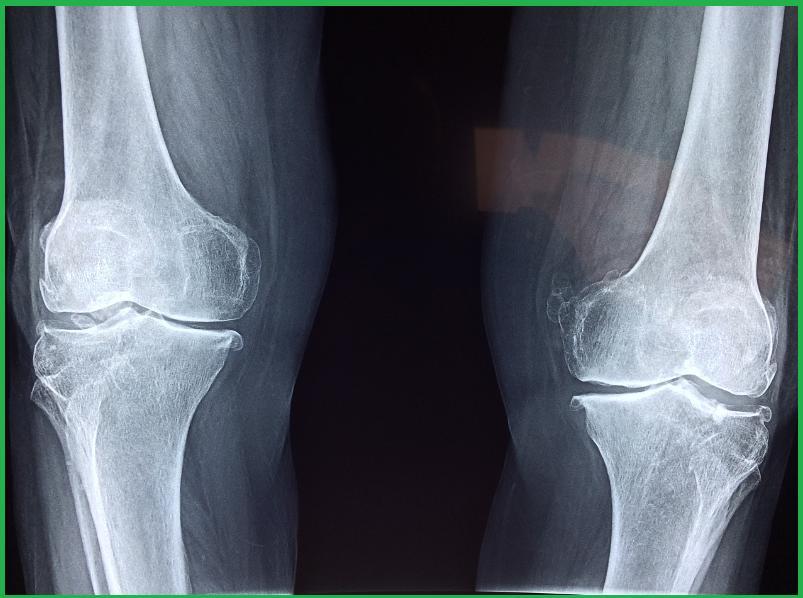

2) 퇴행성 변화(관절염)

노화와 함께 연골이 닳거나 관절에 염증이 생기는 경우, 관절염이 발생합니다. 대표적인 질환으로는 퇴행성 관절염과 류마티스 관절염이 있습니다.

● 퇴행성 관절염 말기: 연골이 완전히 닳아 무릎 관절이 제대로 기능하지 못할 때 인공관절 치환술을 시행합니다.